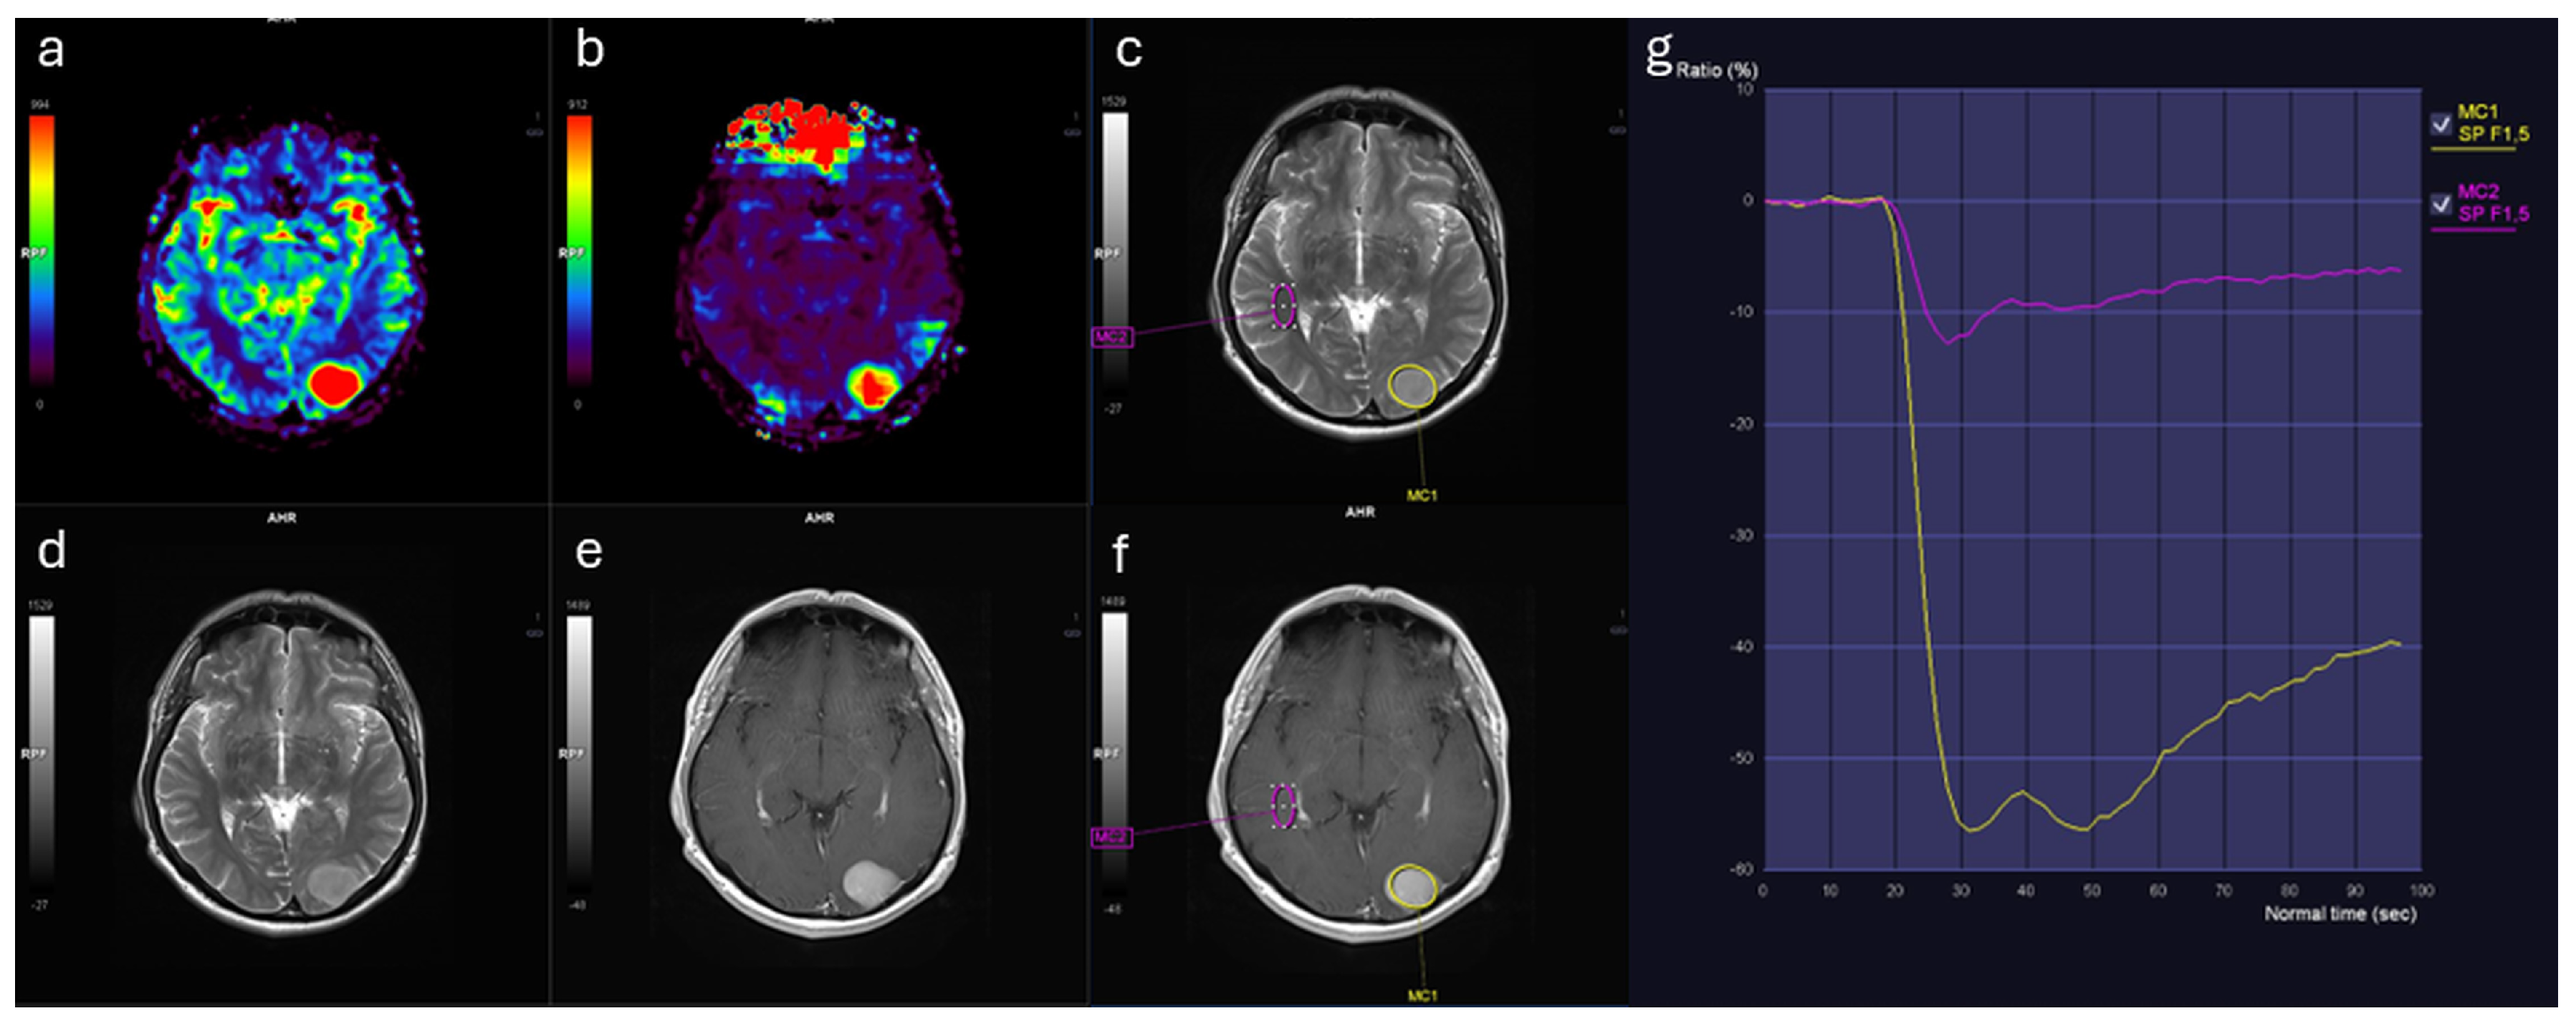

Similarly, rCBF_mean values were markedly elevated in meningiomas (3.44 [IQR: 2.11]) relative to IDMs (2.02 [IQR: 1.10], p < 0.001) (Table 1). Both rCBF_mean and rCBV_mean demonstrated large effect sizes (Cohen’s d > 1.1; η2 ≈ 0.35), indicating marked separation between groups. In contrast, no significant differences were observed between groups in terms of ADC_lesion_mean, rWiT, rPSR, or wash-out slope (Figure 1). Representative perfusion maps and time–signal intensity curves for IDM and meningioma lesions are shown in Figure 2 and Figure 3.

Figure 3. Brain MRI findings in a male patient with atypical meningioma (WHO Grade 2). (a) Relative cerebral blood volume (rCBV) map demonstrates markedly increased perfusion. (b) Relative cerebral blood flow (rCBF) map shows corresponding elevated flow. (c) T2-weighted image with region of interest (ROI, yellow contour) placed within the solid portion of the lesion. (d) T2-weighted image illustrates lesion morphology. (e) Contrast-enhanced T1-weighted image depicts homogeneous enhancement. (f) Contrast-enhanced T1-weighted image with ROI in contralateral normal-appearing white matter (pink contour). (g) Time–signal intensity curves: lesion (yellow curve) reveals higher perfusion and distinct kinetics compared to white matter (pink curve).